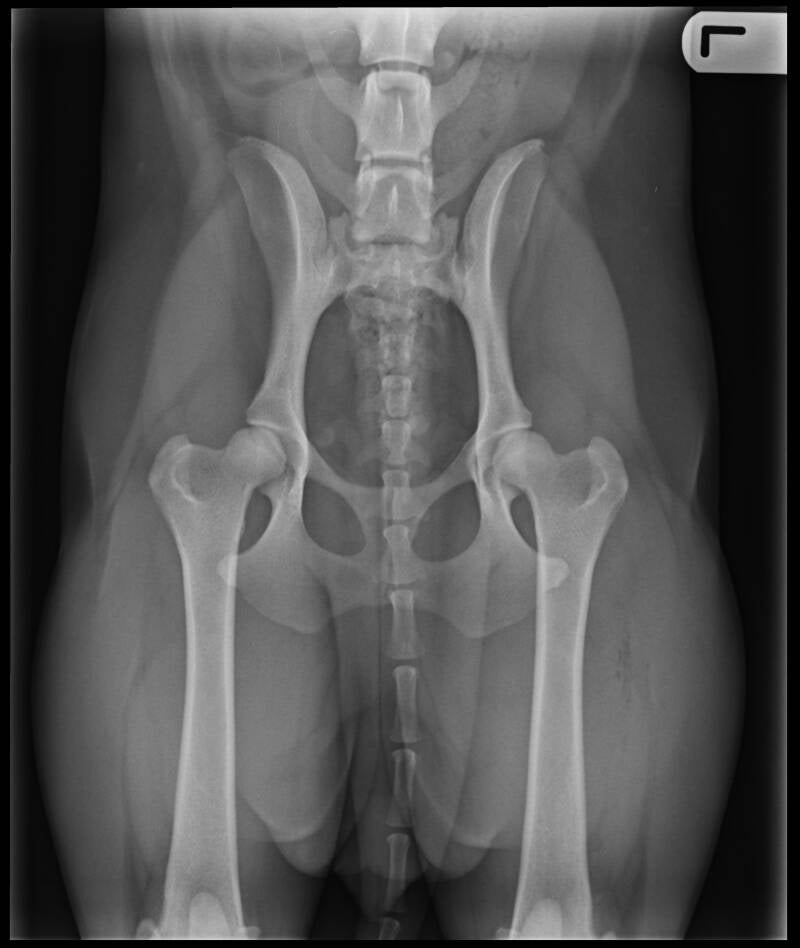

In het najaar starten we met Detectie, Fimke speurt op wiet en we beleven hier veel plezier aan. Voorjaar 2019 de uitslag van de heupfoto's is binnen: HD A, Norbergwaarde 30, geen botafwijkingen. Fimke vangt haar 1e mol, en de 2e en de 3e.........een echte Stabij.